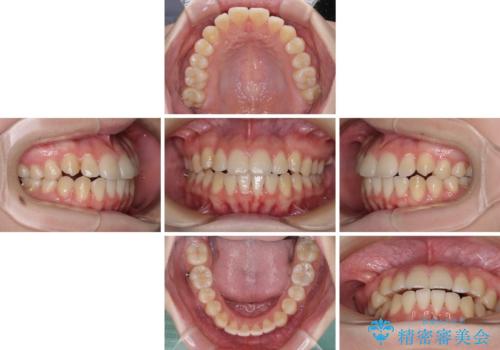

カリエール・ディスタライザーとインビザラインを用いた八重歯の改善

- 前歯の叢生と上顎左右の八重歯を気にして来院された患者様です。

奥歯の咬み合わせを見ると、左側は上顎が下顎に対して相対的に前方にあり、上下の前歯が接触していない状態でした。

咬み合わせを改善するためには、左側上顎臼歯を後方に移動させた咬み合わせにする必要があります。

インビザライン単体で改善することも可能性もありますが、インビザライン単体で達成する可能性が低いと考えられたため、カリエール・ディスタライザーという補助装置を併用して、より確実性を上げることとしました。

奥歯の咬み合わせを改善しながら、並行してインビザラインで歯列を整えることとしました。

カリエールディスタライザーを併用したことで、左側臼歯の咬み合わせを確実に改善させることができました。